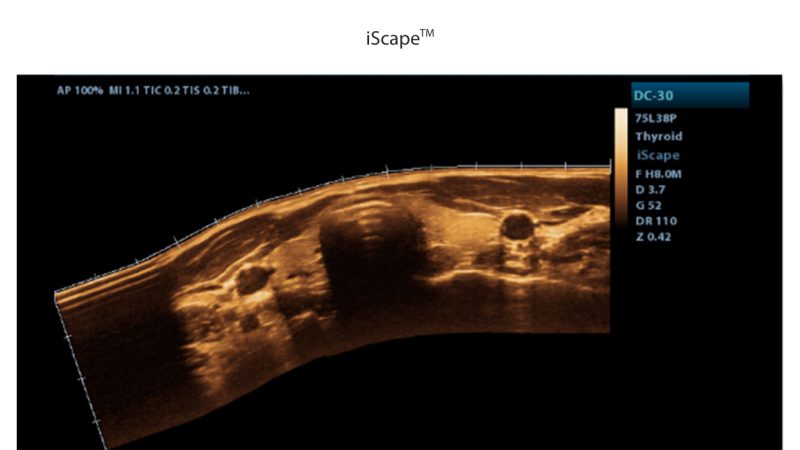

- iScape, Get a complete and extended view of the anatomical structure through panoramic imaging coupled with velocity indication and forward/backward scan ability making scanning much easier, smoother, and more controllable.